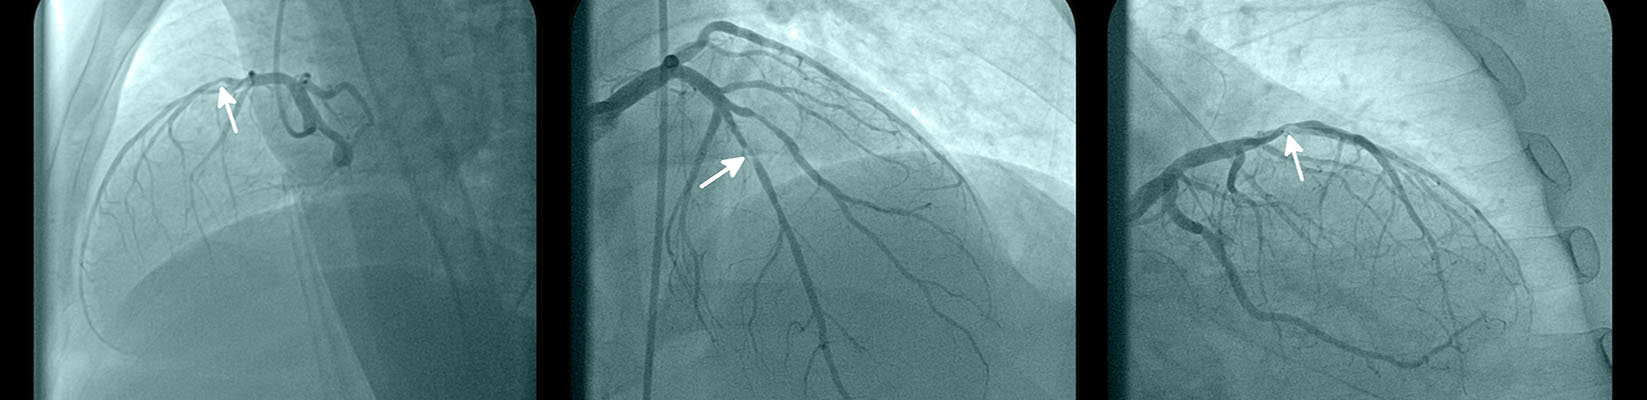

Interventional cardiology involves diagnosing and treating conditions of the heart and blood vessels using nonsurgical, catheter-based procedures and specialized imaging.